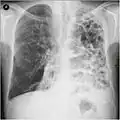

A chest X-ray is not useful to establish a diagnosis of COPD, but it is of use in either excluding other conditions or including comorbidities such as pulmonary fibrosis and bronchiectasis. Characteristic signs of COPD on X-ray include hyperinflation (shown by a flattened diaphragm and an increased retrosternal air space) and lung hyperlucency.[5] A saber-sheath trachea may also be shown that is indicative of COPD.[111]

A lateral chest X-ray of a person with emphysema, displaying barrel chest and flat diaphragm